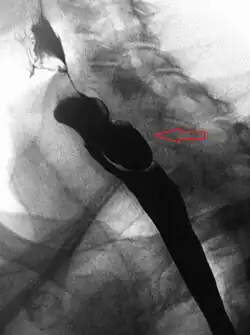

A Zenker's diverticulum, also pharyngeal pouch, is a diverticulum of the mucosa of the human pharynx, just above the cricopharyngeal muscle (i.e. above the upper sphincter of the esophagus). It is a pseudo diverticulum or false diverticulum (only involving the mucosa and submucosa of the esophageal wall, not the adventitia), also known as a pulsion diverticulum.

When there is excessive pressure within the lower pharynx, the weakest portion of the pharyngeal wall balloons out, forming a diverticulum which may reach several centimetres in diameter.

While traction and pulsion mechanisms have long been deemed the main factors promoting development of a Zenker's diverticulum, current consensus considers occlusive mechanisms to be most important: uncoordinated swallowing, impaired relaxation and spasm of the cricopharyngeus muscle lead to an increase in pressure within the distal pharynx, so that its wall herniates through the point of least resistance (known as Killian's triangle, located superior to the cricopharyngeus muscle and inferior to the thyropharyngeus muscle. Thyropharyngeus and cricopharyngeus are the superior and inferior parts of inferior constrictor muscle of pharynx respectively). The result is an outpouching of the posterior pharyngeal wall, just above the esophagus.[3]

A combination of the simple barium swallow and a thorough endoscopy will normally confirm the diverticulum.[4]

If small (ie, <2 cm) and asymptomatic, no treatment is necessary.[5] Larger, symptomatic cases of Zenker's diverticulum have been traditionally treated by neck surgery to resect the diverticulum and incise the cricopharyngeus muscle. However, in recent times non-surgical endoscopic techniques have gained more importance (as they allow for much faster recovery), and the currently preferred treatment is endoscopic stapling[6][7] (i.e. diverticulotomy with staples ). This may be performed through a diverticuloscope. Other methods include fibreoptic diverticular repair.[8]